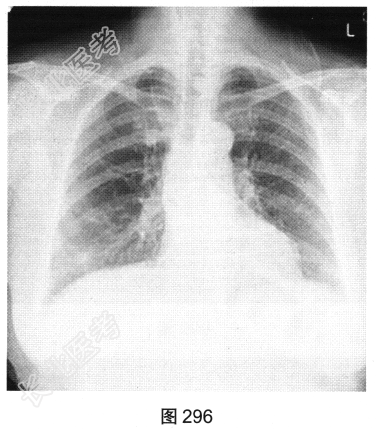

- [材料题] 患者女性,38岁,咳嗽、咳白痰10个月,伴活动后喘憋,无发热、盗汗、咯血、胸痛、胸闷、腹泻、腹胀等。胸部X线片如图296、图297所示。

- 多项选择题1.从患者的胸部X线片中可见哪些阳性征象( )

A、双肺纹理增粗

B、右肺尖高密度结节

C、右肺下野高密度斑片影

D、双侧肋膈角钝

E、双肺门增大

F、右肺下野囊状透亮影